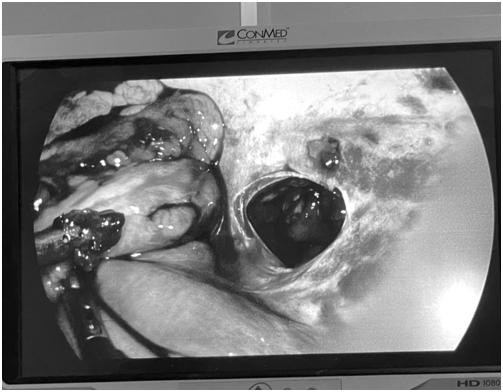

| Hình ảnh chụp chiếu cho thấy vết thương do dao đâm rộng khoảng 3cm đang chảy máu |

Các bác sĩ đã tiến hành sơ cứu băng ép vết thương, đặt đường truyền và đưa bệnh nhân đi chụp Cắt lớp vi tính. Qua hình ảnh cắt lớp vi tính, các bác sĩ nhận định trường hợp này là một vết thương thấu bụng có tổn thương vào đại tràng xuống, chỉ định mổ cấp cứu xử trí tổn thương. Ngay lập tức, bệnh nhân được chuyển lên phòng mổ.

Sau khi kiểm tra toàn bộ ổ bụng, kíp mổ nhận định trường hợp này tổn thương xuyên 2 thành đại tràng xuống, không có tổn thương cơ quan khác, quyết định đưa đoạn đại tràng tổn thương ra ngoài làm hậu môn nhân tạo tạm thời, lau rửa sạch ổ bụng, và khâu đóng vết thương thành bụng bên trong, đặt 2 dẫn lưu ổ bụng.